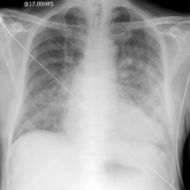

تظهر العلامات الشعاعية عادة قبل ظهور العلامات السريرية وأولى هذه العلامات هي تشوش الحدود الواضحة للأوعية الرئوية الرئيسية في السرتين مع تغيم منتشر في الرئتين (منظر الغشاء المغشى).

وكلما تطورت الوذمة ظهرت كثافات عقدية إضافة إلى علامات تكثف سنخي وازدادت الكثافة في السرتين وتدعى علامة جناحي الخفاش Wing Bat’s وهي علامة مميزة.

ومن العلامات الشعاعية المرافقة وجود دليل على إصابة قلبية بدئية كضخامة البطين الأيسر، كما أن زيادة الضغط في الأذينة اليسرى وزيادة الضغط الخلالي قد يسببان نقصاً في ضخ الأوعية الرئوية إلى الأقسام السفلية من الرئتين وبالتالي إلى تحول الجريان إلى الأقسام العلوية.